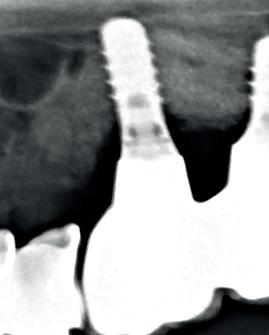

Am 13. Februar 2024 wurde das aktuelle Economist Impact Whitepaper veröffentlicht, das von der EFP (European Federation of Periodontology) mit Unterstützung von Haleon erarbeitet wurde.

Es gibt Einblick in die Zusammenhänge zwischen der zunehmende Belastung durch orale Erkrankungen (Parodontitis und Karies) und globale Ungleichheit, hebt die Zusammenhänge zwischen diesen beiden Krankheiten hervor, stellt einen kombinierten Ansatz zur Verbesserung der Mundgesundheit und der systemischen Gesundheit der Bevölkerung vor und präsentiert einen Kostenrechner für die Kariesprävention und -behandlung.

Prevalence of the 2 most common oral diseases Combined: 3,639m

Figure 1: Comparison of estimated global case numbers for selected NCDs

Prevalence of 5 of the most common NCDs Combined: 2,494m

Source: Global Burden of Disease, 201945 Dental caries 2,551m Severe periodontitis 1,087m Mental disorders 970m Cardiovascular disease 523m Diabetes 460m Chronic respiratory disease 455m Cancer 86m